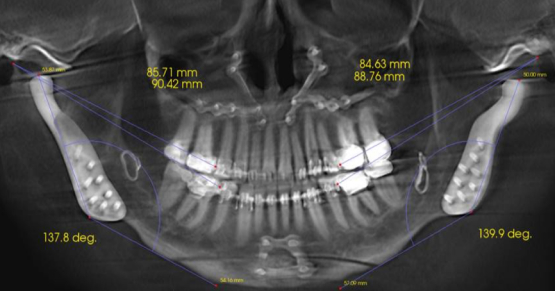

Not all discolored teeth are responsive to conservative approaches like nightguard vital bleaching (NGVB) or non-vital bleaching. Even if an excellent initial outcome is achieved, sometimes relapse occurs. Therefore, when bleaching fails, restoration consideration should be given to a masking procedure using indirect or direct composite resin veneers.

The exception is teeth that are structurally compromised, such as endodontically treated teeth with extensive Class III restorations.